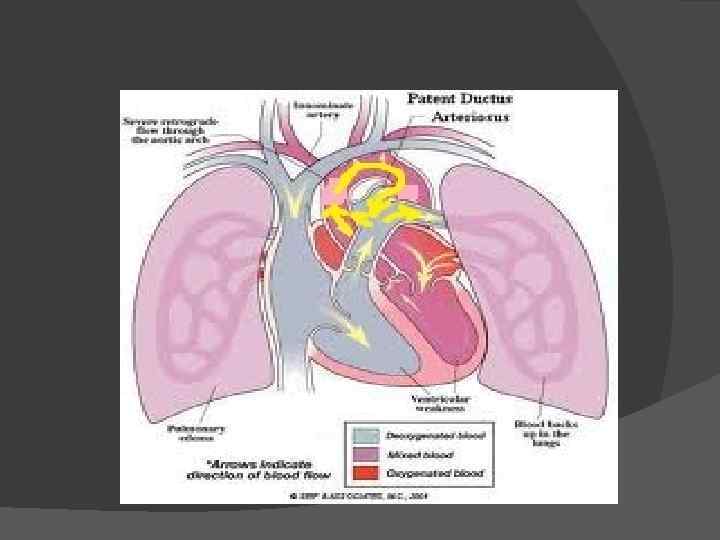

Первичное нарушение гемодинамики связано с разницей давления в аорте и легочной артерии. Через открытый артериальный проток кровь течет из аорты, где давление выше, в легочную артерию.

Следовательно, известная часть крови, выбрасываемая левым желудочком в аорту, переходит непосредственно в легочную артерию и через легкие, легочные вены и левое предсердие возвращается опять в левый желудочек

В результате правый желудочек компенсаторно гипертрофируется и расширяется. Расширяется и легочная артерия, которая наполняется кровью под большим давлением. Таким образом, артериальная кровь добавляется к венозной, следовательно, возникает сброс слева направо. Количество сбрасываемой крови различно в зависимости от соотношения диаметров протока и аорты.